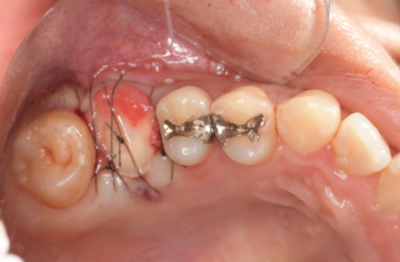

移植手術後

右上6抜歯1ヶ月後、移植手術を行った。

右下8を抜歯し右上6部に移植、縫合糸で固定した。

移植手術後、治癒に異常を認めなかったため、移植2週間後に根管治療を行った。